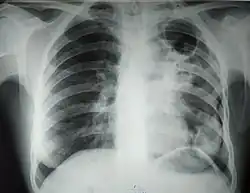

![]() Рентгенограмма органов грудной клетки больного туберкулёзом лёгких с распадом | |